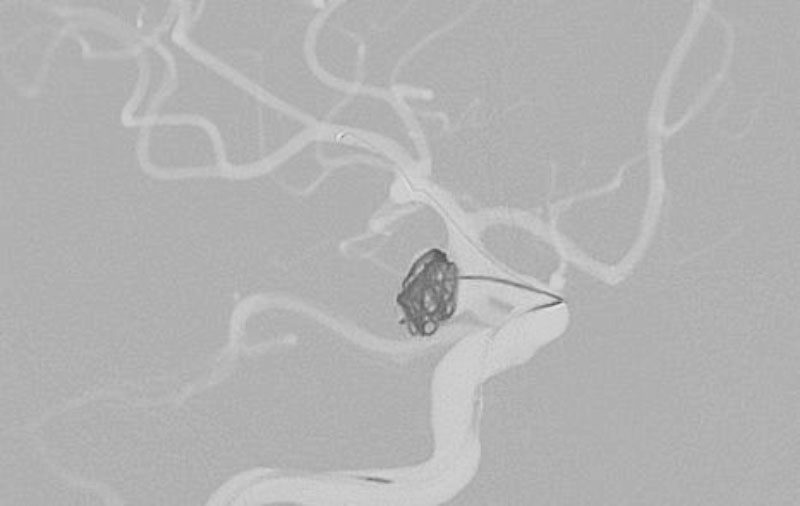

No.1631 手術中